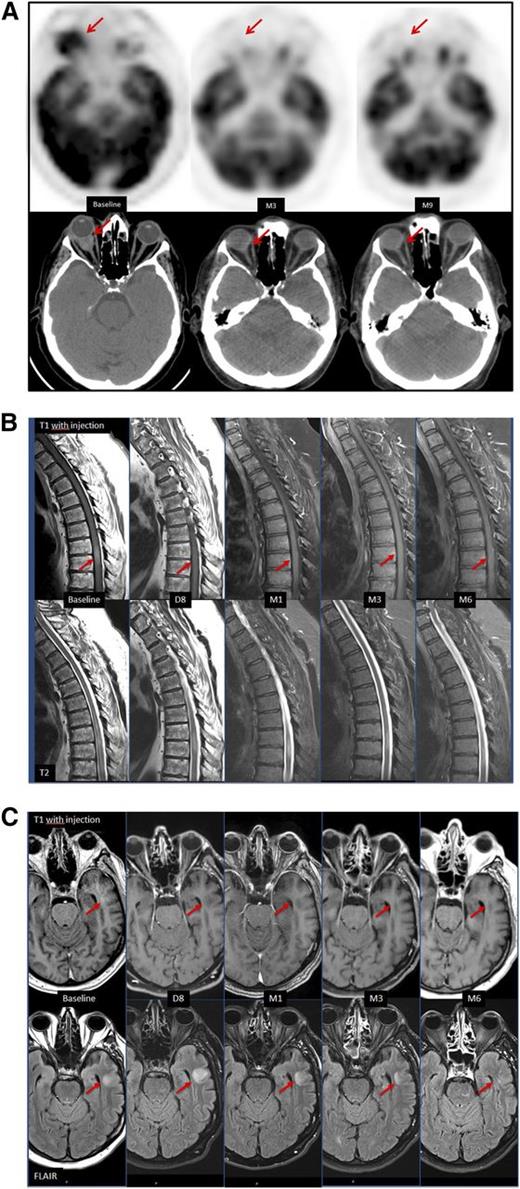

Neuroimaging in patient 1 and patient 2 under ibrutinib treatment. (A) Patient 1. CT without contrast and FDG-PET of the orbits at baseline, and at 3 and 9 months. Assessment at 3 months showed a CR. A clinical response was observed after 2 weeks of initiation of ibrutinib. (B-C) Patient 2. Contrast-enhanced T1-weighted (top) and T2-weighted (bottom) MRI of the spine (B), and contrast-enhanced T1-weighted (top) and FLAIR images (bottom) of the brain (C), at baseline, day 8, and at 1, 3, and 6 months. At day 8, CR was observed in the spine and the brain without remaining contrast enhancement. Anomalies on T2-weighted images took up to 6 months to clear in the brain.

At 3 months, impressive responses had been obtained for all 3 patients (Figure 1). The first patient presented a complete response (CR) for cerebral and extracerebral lesions according to Lugano classification criteria8 at 3 months, which was maintained at 6 months, with a normal computed tomography (CT) scan and a negative FDG-PET scan of the CNS retro-ocular lesion. The follow-up for this patient is currently at 1 year and he is still in CR as seen on FDG-PET, cerebral MRI, and CT scan. The second patient showed very early improvement in his neurologic exam (within 3 days). In parallel, we observed a reduction of CNS lesion on MRI at day 8, with a CR at 1 month on cerebral MRI, medullar MRI, and FDG-PET. At 6 months, the CR was confirmed at both sites on cerebral and medullar MRI. The third patient presented a partial response (PR) in CSF (decrease from 900 to 76 cells/mL) and retro-orbital lesion evaluation (cerebral MRI) with recovery of walking, decreased pain, and improved performance status. All 3 responses occurred within 3 to 8 days of treatment initiation, with a significant improvement in the clinical examination. Response was confirmed in all cases by biological analysis and imaging. Only 2 cases (patients 2 and 3) were evaluated for CSF infiltration, and one of them was positive. Patients obtained a clinical response in the 3 cases, with no consideration of CNS relapse site and CSF infiltration. We did not observe any secondary effect in terms of bleeding or hematoma when performing lumbar puncture under ibrutinib.